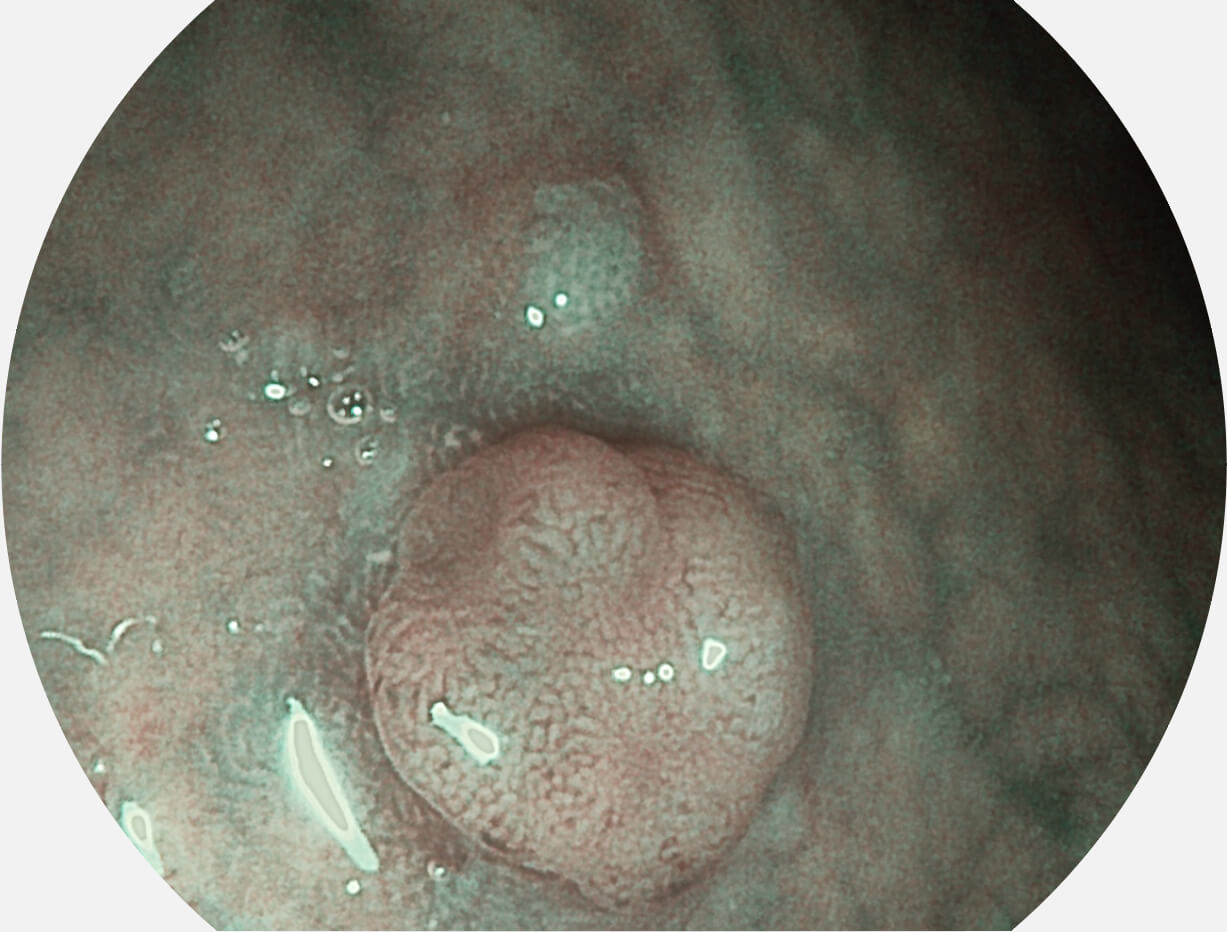

• 白光图像 SFI图像

图像具有高亮度、高黏膜血管颜色对比度的特点,且不改变粘液、食物残渣、粪便的基本颜色,可在中远景下进行观察,助力消化道早期疾病的诊断。